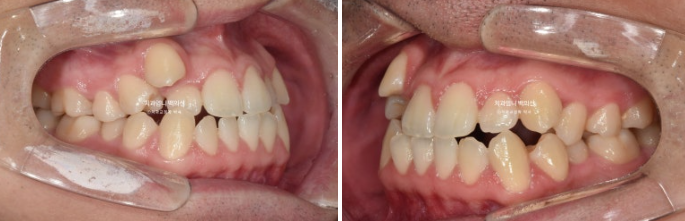

2022.09

덧니가 심해서 작은어금니 4개 발치가 불가피한 상황입니다.

약간의 입술돌출도 함께 해소하기로 했습니다.

인비절라인으로 치료 시작했으며 장치제작기간을 한달 반을 기다려 10월부터 인비절라인 1번 장치를 끼기 시작했습니다.

22.09~25.04